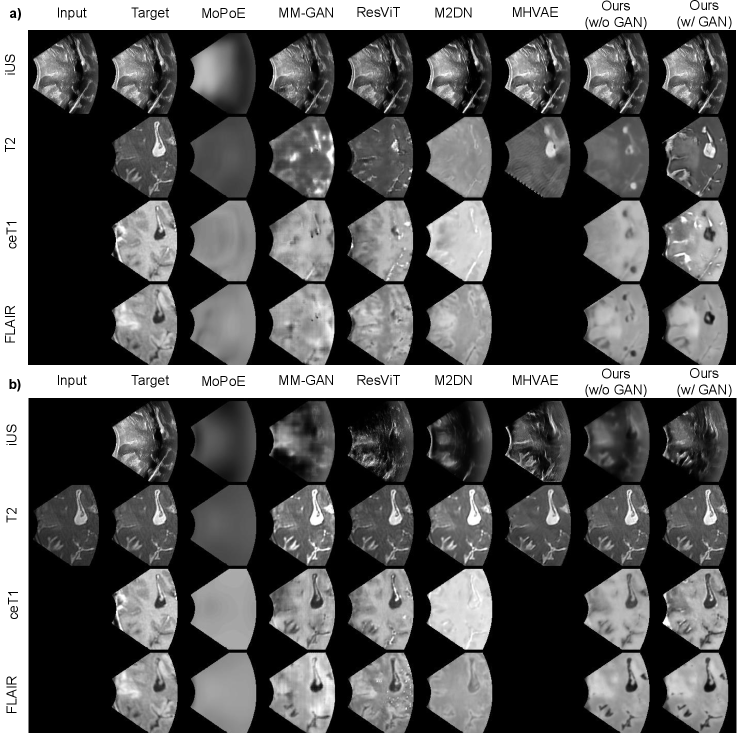

Figure 3: Qualitative comparison of our method with all competing methods for synthesizing all modalities (iUS, T2, ceT1, FLAIR) from (a) iUS; (b) T2. Our approach generates sharper images with better contrast differentiation between tissues and modality-specific patterns (e.g. speckles for iUS).

We first assessed the effectiveness of MMHVAE in performing harmonized cross-modal image synthesis of multi-sequence MRI and ultrasound. MMHVAE was compared against the state-of-the-art unified synthesis framework using convolutional (MoPoE, MM-GAN), transformer (ResVIT), and diffusion models (M2DN). Performance on unified models was evaluated at test time for each possible combination of input images in the ReMIND dataset. Qualitative results are shown in Figure 3, and detailed quantitative results are presented in Table I.

Cross-modal synthesis task: When the target modality is missing in the input set (indicated by an empty circle), the task synthesizes the harmonized missing modality using the available input images. Figure 3 shows qualitative results for various input combinations. Our method consistently outperforms state-of-the-art approaches across all modalities. First, as illustrated in Figure 3, MoPoE produces noticeably blurry images, highlighting its limitations in generating high-quality outputs. In contrast, our approach produces more realistic and detailed images than other unified synthesis methods. Specifically, our method generates synthetic ultrasound images with more realistic textures, such as the presence of speckles, while also better preserving anatomical structures. These qualitative improvements align with the quantitative metrics shown in Table I, where our method achieves lower perceptual LPIPS and higher structural SSIM scores.

Another key component of our framework is the use of the GAN loss. We present results with (λGAN=0.025\lambda_{\text{GAN}}=0.025) and without (λGAN=0\lambda_{\text{GAN}}=0) the GAN loss in Figure 3 and Table II. As shown in Figure 3, using the GAN loss improves the visual quality of the generated images. Without the GAN loss, our model tends to produce smoother and less realistic images, particularly lacking the speckles characteristic of ultrasound images. These qualitative improvements align with the perceptual results in Table II, where lower LPIPS scores are achieved with the GAN loss. However, we also found that the GAN loss leads to lower SSIM and PSNR scores. This illustrates the typical challenge in assessing image synthesis methods, where metrics may not agree.